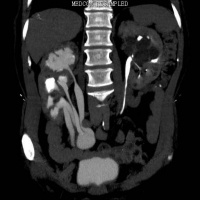

单侧肾四肾盂输尿管

CT检查可清晰显示重复肾畸形及合并积水的双输尿管, 能更清楚的显示重复肾的内容,同时CT连续层面观察可确定输尿管的异位开口,但对无扩张的重复输尿管显示不够清晰,直观。